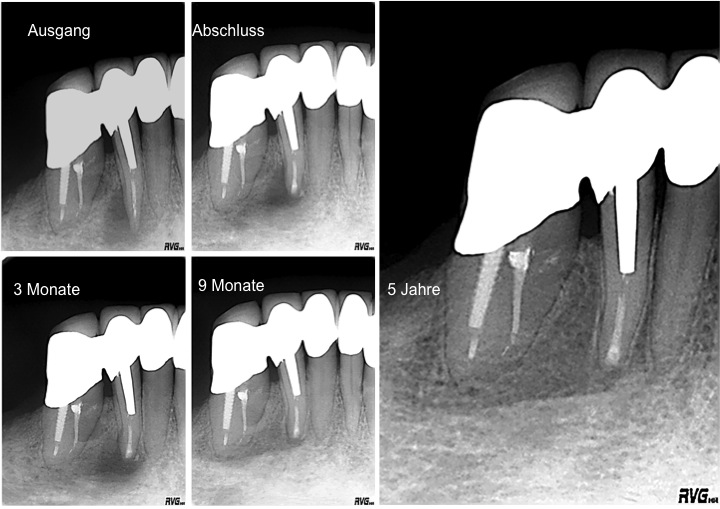

Resektion